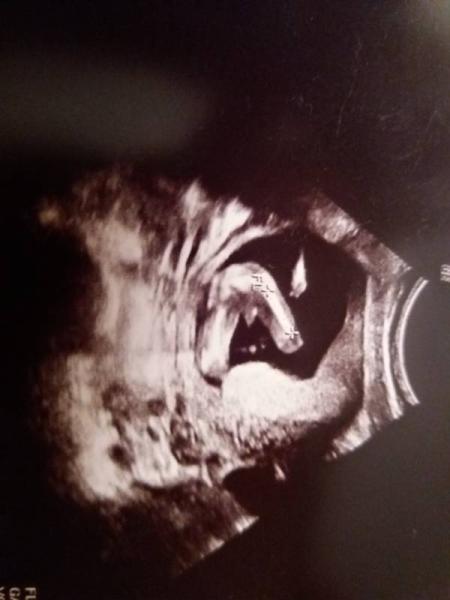

Du meintest in einem Beitrag das deine töchter erst jungs waren? In welcher woche war das. Ich bin heute14+2 und mir wurde gesagt das wir einen jungen bekommen. Ich zeig dir mal das Bild. Sah es bei dir auch so aus? LG steffi

Bild zu @OliviaÖl - Schwanger - wer noch? Rund um die Schwangerschaft